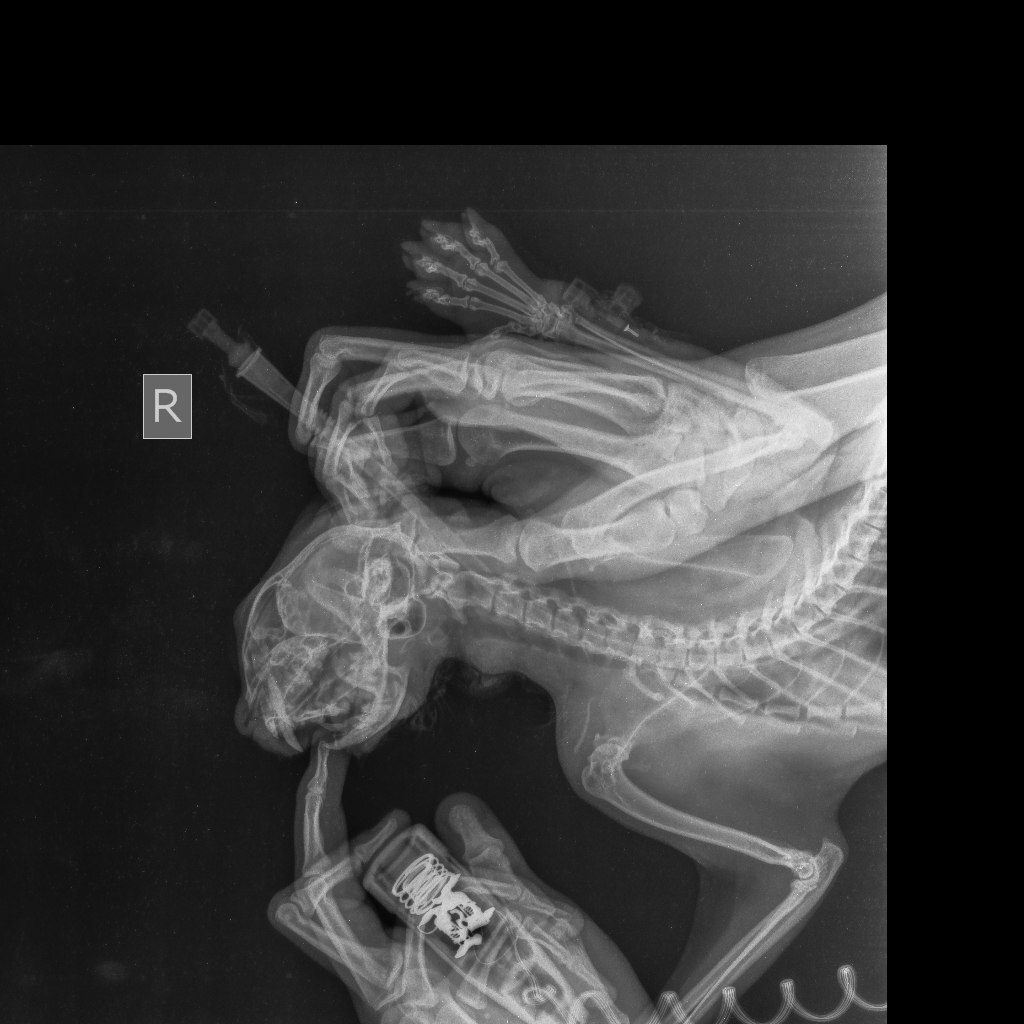

Пока кошка Милка от которой отказались ее же хозяева продолжает лежать у нас, сегодня был разговор со стоматологом.К сожалению стоматолог находится в другой клинике и не может приехать осмотреть животное, но он попросил сделать снимки записать видео, что бы предположить хотя бы какой диагноз у кошки.

После этих манипуляций был поставлен пока предварительный диагноз: Вывих височно- нижнечелюстного сустава?Перелом нижней челюсти по симфизу?

Прикладываю рентгены кошки